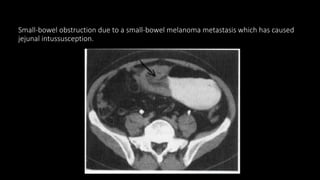

Small-bowel obstruction due to a small-bowel melanoma metastasis which has caused

jejunal intussusception.

 Adult intussusception

• The majority arise from a pathological lead point.

• Causes include lipomas, carcinomas, metastases and lymphoma.